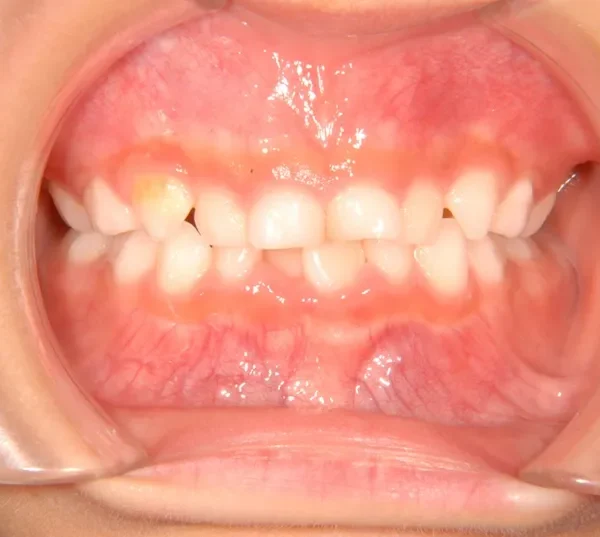

• 治療終了後

治療終了後

治療回数43回、7年4ヶ月の治療期間で矯正治療を終了しました。

主訴が改善され、ご満足頂きました。